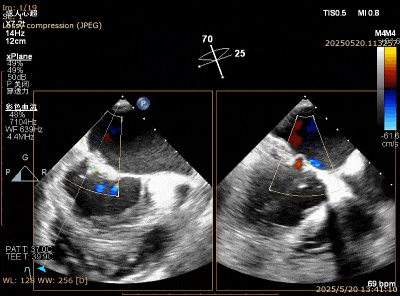

在一些退行性二尖瓣(DMR)病例中,由于二尖瓣连枷瓣叶甩动厉害,两个瓣叶之间的连枷间隙过大,难以充分夹合瓣叶:二尖瓣瓣叶甩动形成了拱形结构,经股静脉夹子摆动式的设计只能捕获到拱形的下降支,或在关闭时瓣叶仍在甩动导致瓣叶滑脱。一些技巧可以帮忙克服这一难点,包括快速起搏、腺苷或者拉链技术,但这些操作都偏复杂。一个简单方法就是将下夹臂反转到210度以上,让瓣叶充分插入到上下夹臂之间夹角内,然后较快速关闭夹子(图5-7)。该方法可以配合分别捕获技术提高夹合的成功率。无论刚性夹和弹性夹,该技术都可以应用。

图5. Barlow样改变,A3,P2, P3脱垂,后叶甩动厉害

图6. XTR 一枚夹合 2区,后叶难以夹多

图7. 倒挂金钩,夹合更多瓣叶